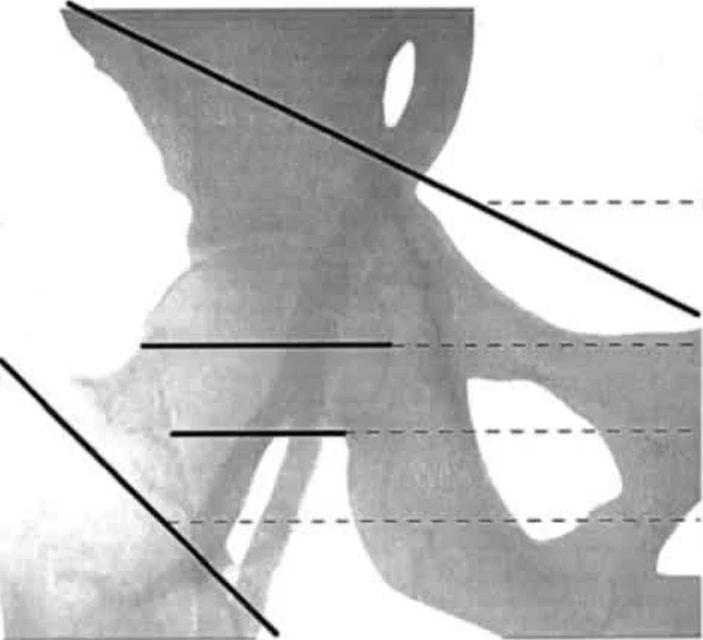

不同的人,腹股沟韧带和皮肤褶皱距离变异较大,一般为0~11㎝之间,平均6.5㎝;

股动脉分叉大部分位于腹股沟皮肤褶皱以下,此处血管分支且血管较为细小,并发症发生概率增大且不利于操作;

因此以腹股沟皮肤褶皱下方X㎝作为穿刺点不可取。

(图源:介入心脏病学第二版)

92.7%搏动最强处位于股动脉处,腹股沟韧带下方股动脉搏动最强处作为穿刺点是可取的。

不过因为测量的搏动最强处为一个范围,因此股动脉搏动最强点结合腹股沟韧带下方3㎝处可作为穿刺参考点。

透视下股骨头可选原因

当患者血压特别低,股动脉搏动非常弱的情况下,不能通过触摸的方法确定穿刺参考点,可通过透视方式实现。

皮肤穿刺点位于股骨头下缘,进针方向在股骨头中点内测。